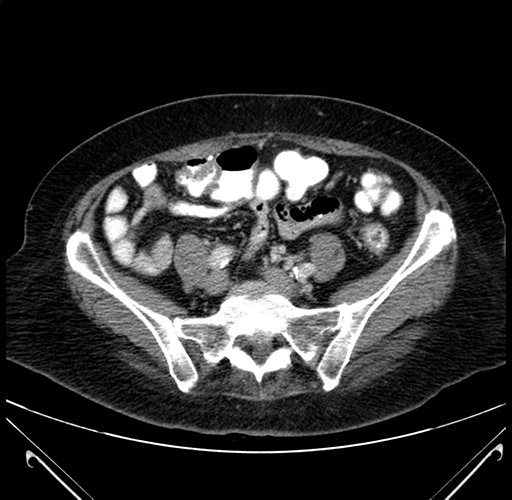

Pre-Chemo: Axial Venous

Axial Venous